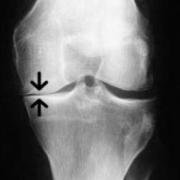

The Unloader Brace is designed specifically for active people who have arthritic damage on just one side of the joint. The idea is to reduce the forces through the joint cartilage of one side of the knee when cartilage damage is still restricted to just one half of the joint.

Unloaders are often used to give symptomatic relief to patients whose knee osteoarthritis is not severe enough to warrant a total knee replacement, or to patients who are waiting for a knee replacement, either a total or a partial one. They are also used to 'unload' one side of the knee after cartilage repair surgery.